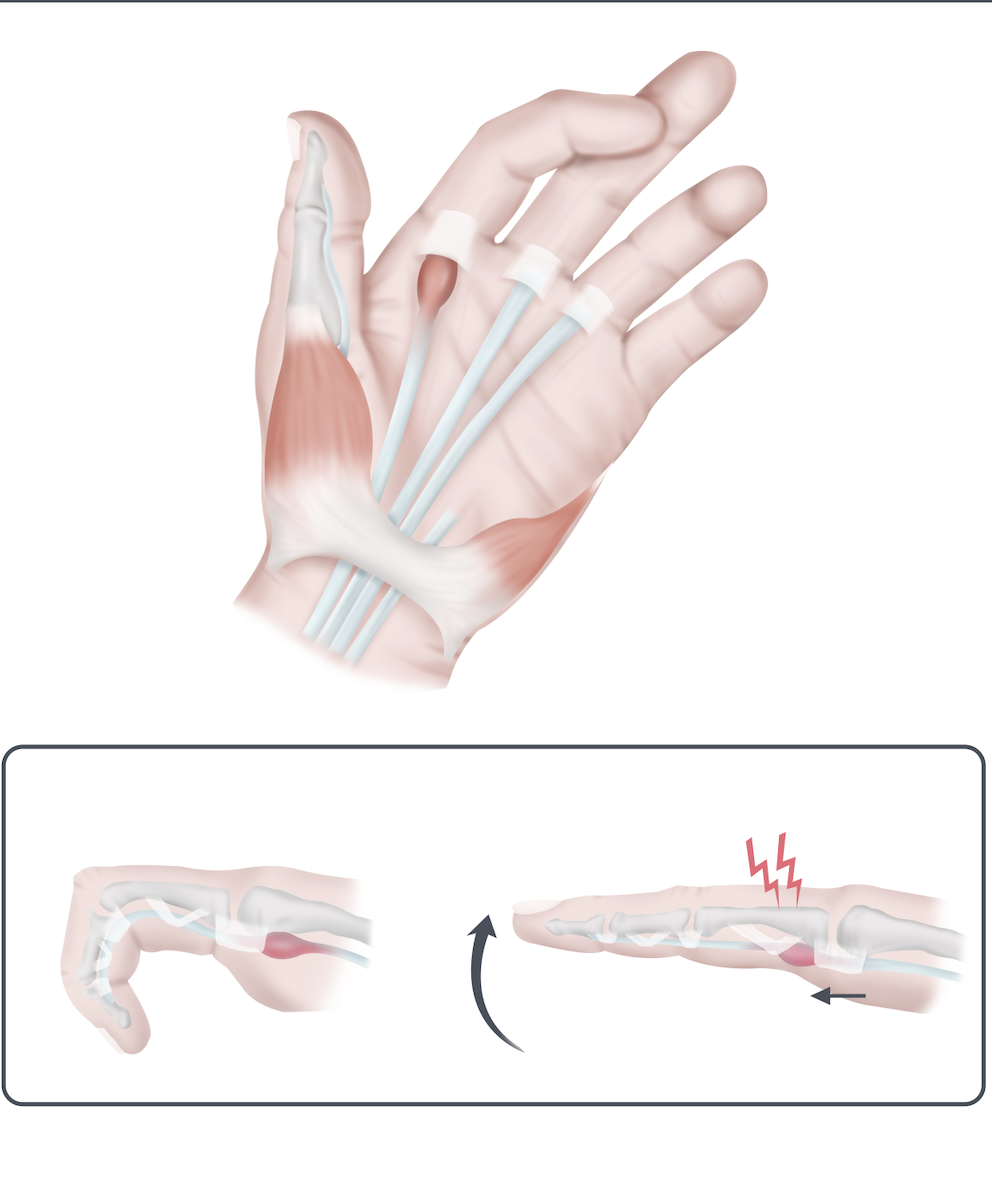

发现扳机指和掌腱膜掌腱膜之间的联系

发现扳机指和掌腱膜挛缩症之间的联系作者:Tayer Roost 参考文献:Yang, Gehring, M.、Bou Zein Eddine, S. 和 Hettinger, P. (2019)。狭窄之间的关联...